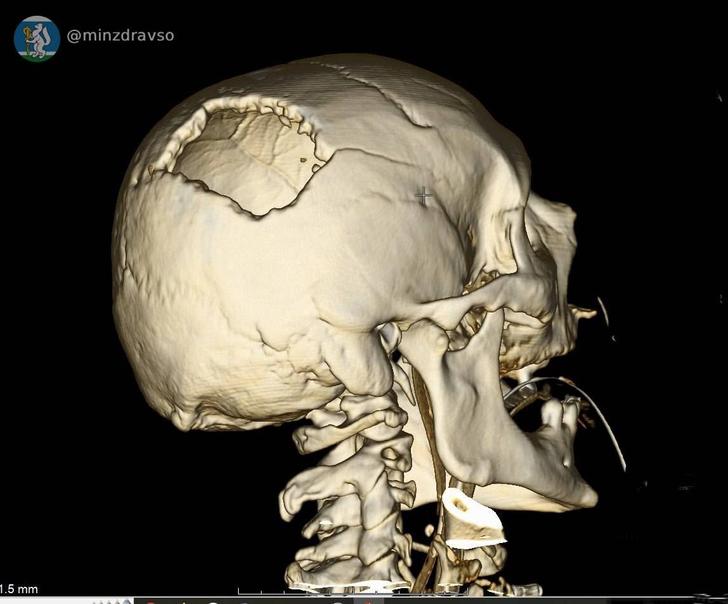

Мужчине сделали компьютерную томографию, чтобы увидеть его травмы и понять, где находятся повредившие мозг костные отломки. Самый острый из них мог в любую минуту привести к смерти, сообщили в Департаменте информационной политики Свердловской области.

- удалили отломки костей и гематомы;

- восстановили целостность твёрдой мозговой оболочки.